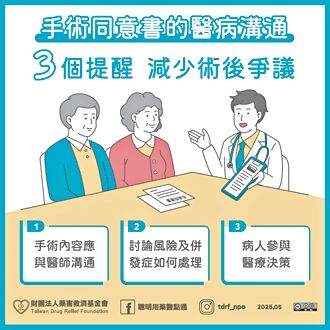

簽手術同意書前 勿忘3大溝通重點

民眾在進行手術、麻醉或侵入式檢查前,會由醫師提供說明,並簽署同意書。手術同意書本意是建立治療共識,但當醫療爭議發生時,同意書可能成為訴訟的證據。藥害救濟基金會提醒,簽署手術同意書時有3大溝通重點。